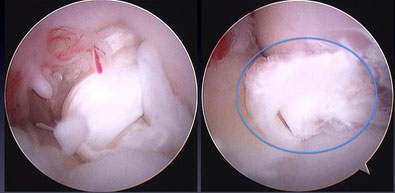

↓これは、いちくんの内視鏡画像ではないのですが、白くフワフワしたのが切れてしました前十字靭帯です。

情報収集している時に、このフワフワした前十字靭帯をノズルみたいなので吸い取ってる動画を見たので、恐らく同じ様な処置をされたのだと思います。